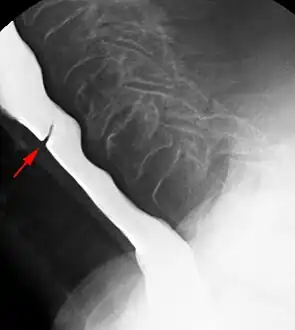

Esophageal web stenosis in barium swallow examination lateral view.

Web with "jet-phenomenon". Arrowhead on incomplete opening of the upper esophageal sphincter.